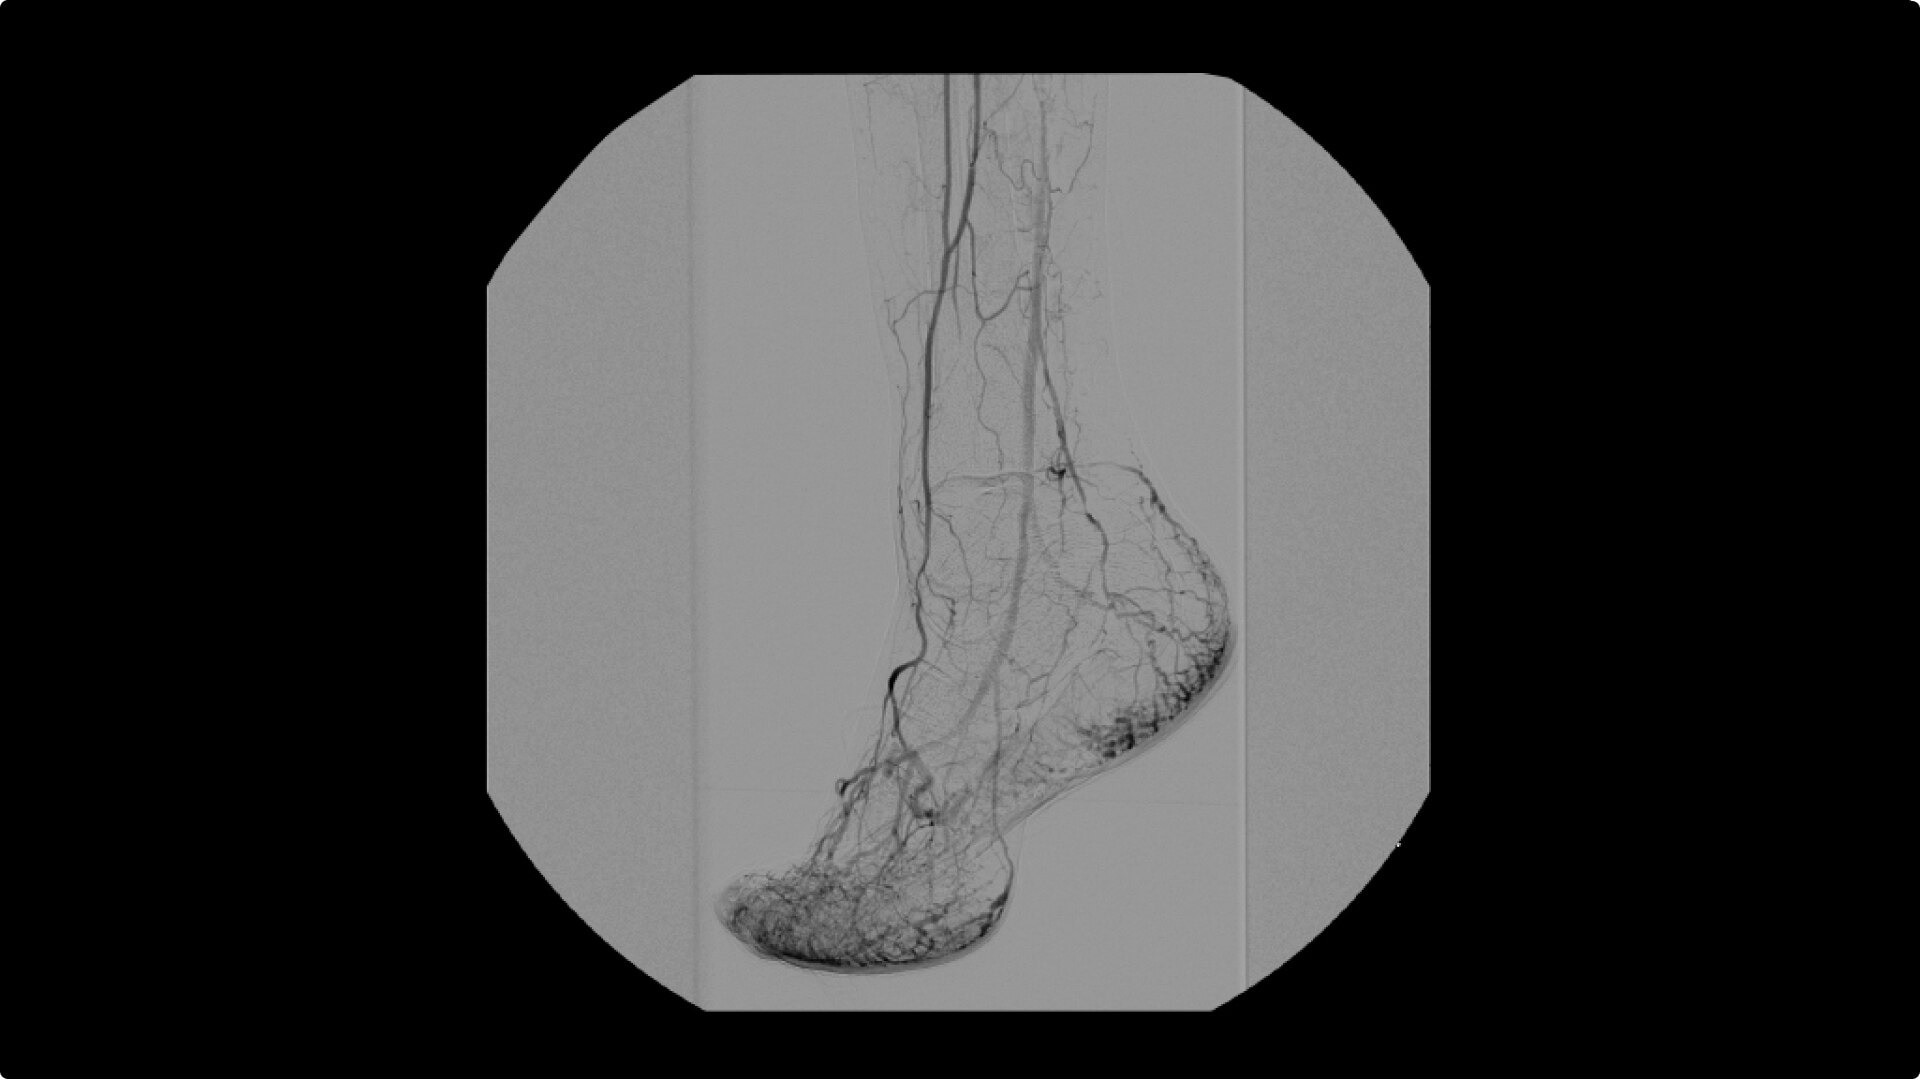

OEC C-arms are used by interventionalists and surgeons to obtain vascular imaging during peripheral to contrast run-off procedures. Superb resolution, even in the presence of motion, enables easy identification of anatomical landmarks and the extremity of the catheter, even as catheter tip moves.

Perform a full leg Bolus Chase in one contrast run with a Preset Profile that includes Motion Tolerant Subtraction, that dynamically adjusts image quality based on presence of motion.

During contrast run-off procedures, easily select contrast type with positive (e.g. Iodine) or negative (e.g. Carbon Dioxide) during subtraction. The OEC Elite CFD cardiovascular package also includes Roadmapping.

To see vessel stenosis or tips of guidewires, Live Zoom up to 4X during a fluoro or Cine without the additional dose of Mag modes or resulting X-ray tube heat buildup.